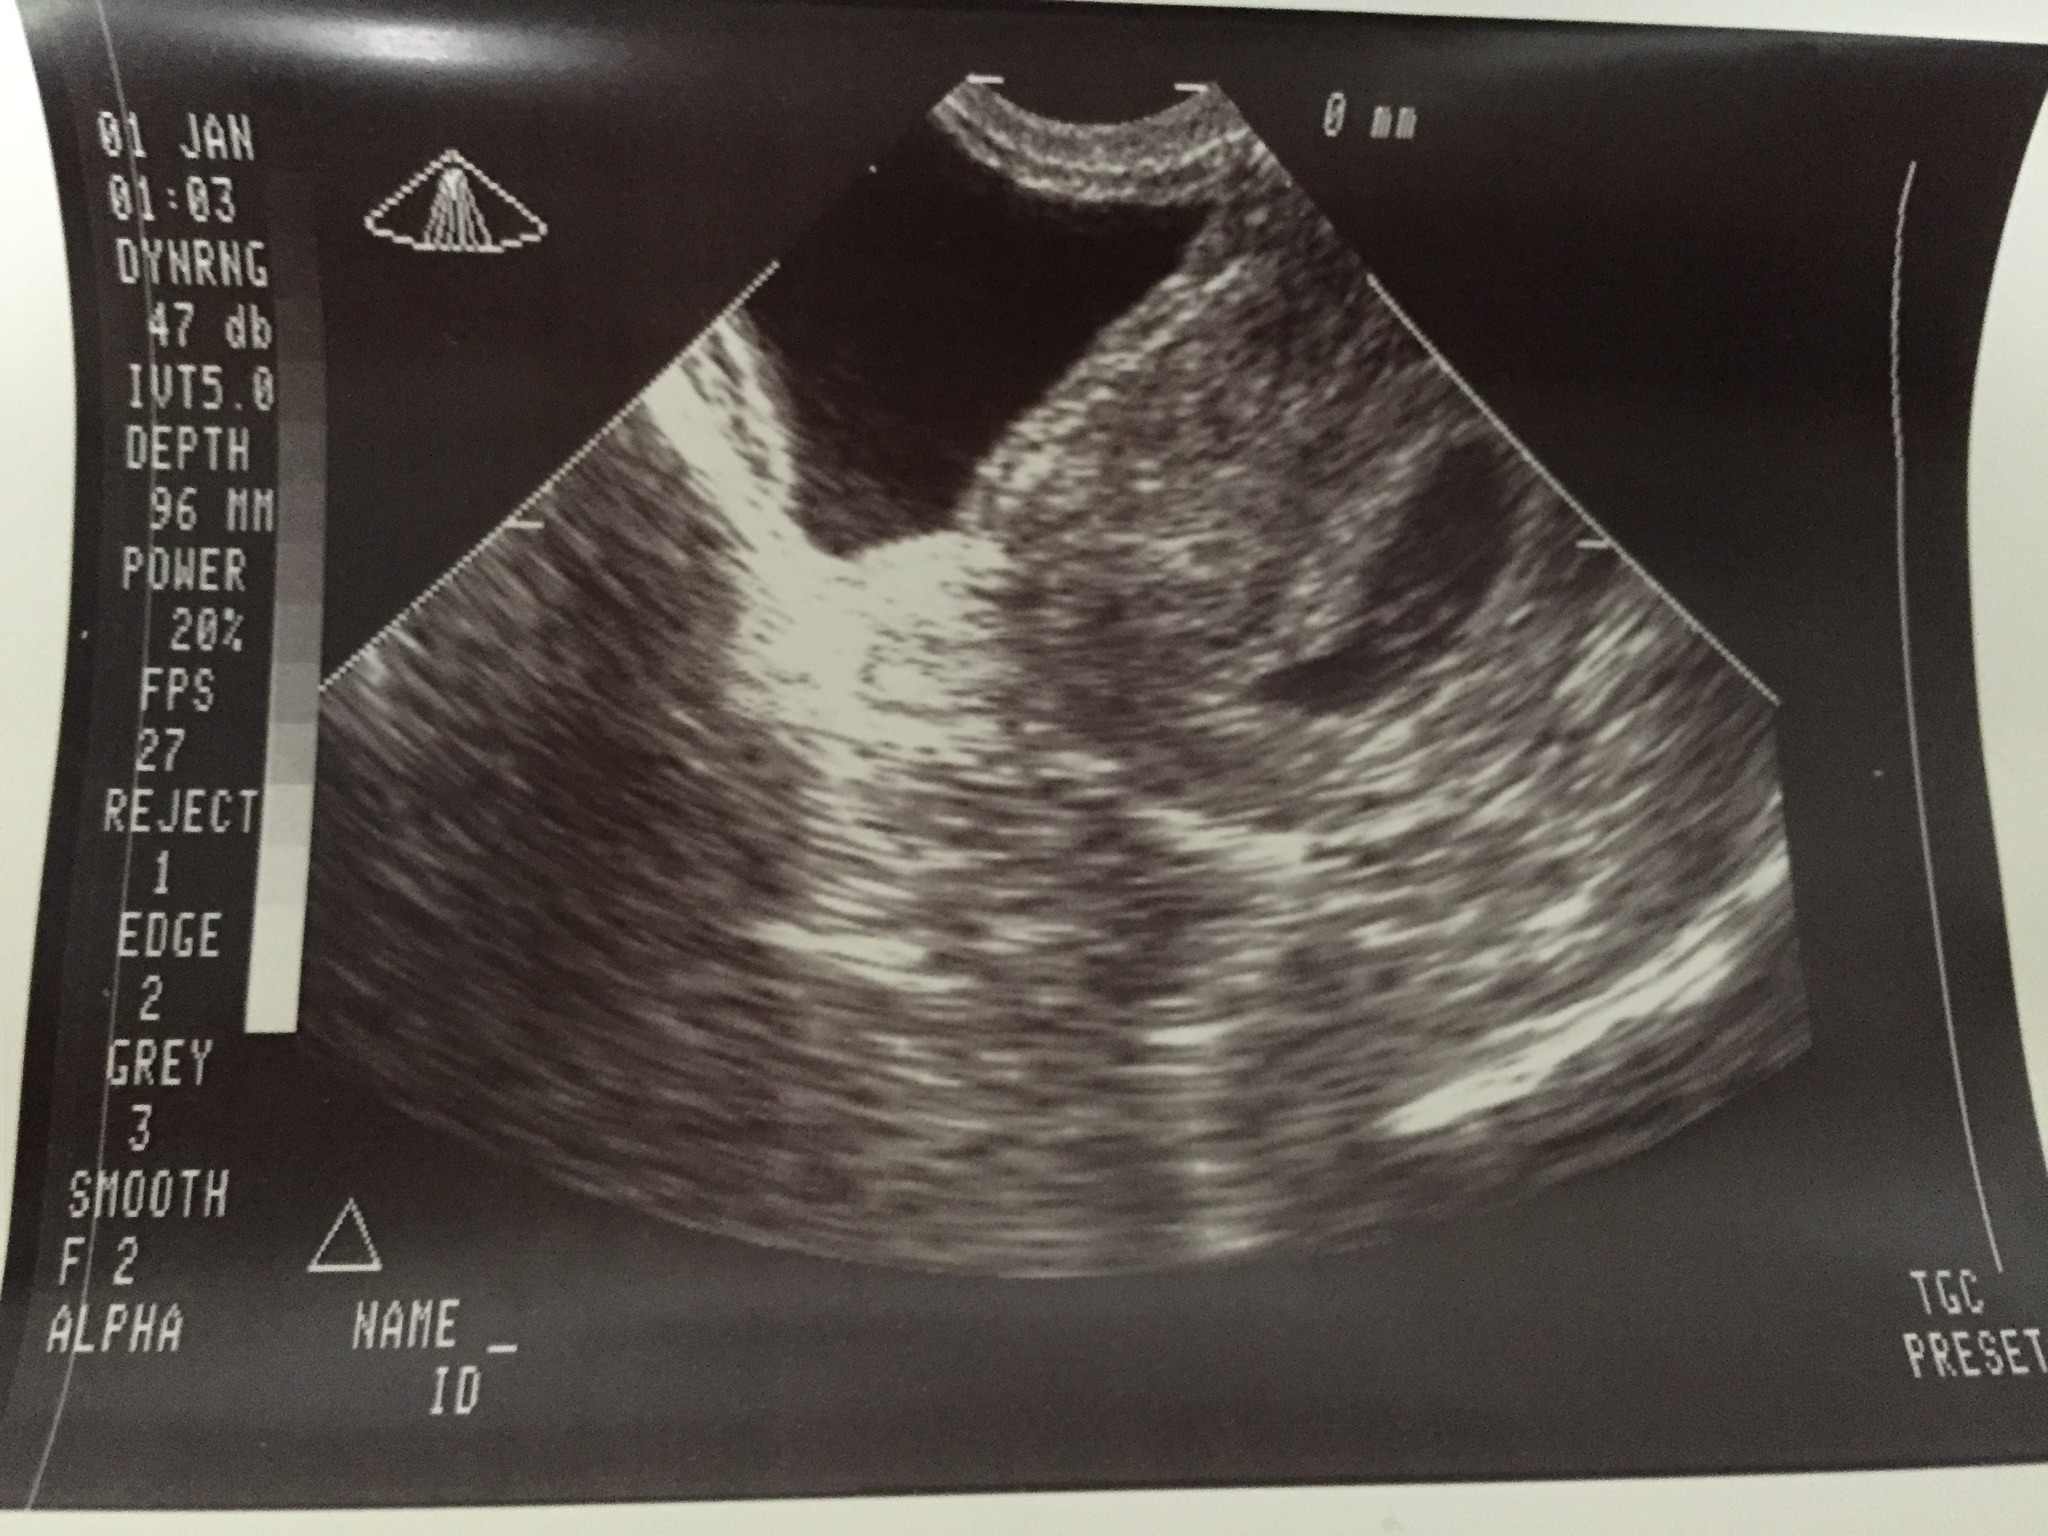

This was a transvaginal ultrasound done a few weeks back.